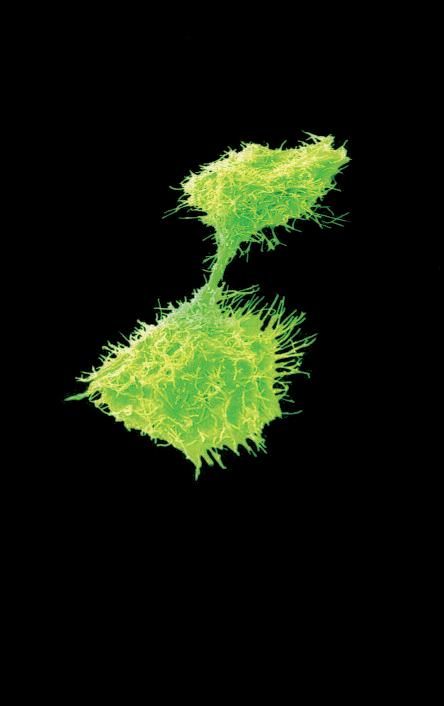

„Brillano di rosso le stelle?”

„La scienza pari all’ar te“ un’idea di August Kowalczyk

„Brillano di rosso le stelle?” immagine al microscopio di cellule tumorali, che per effetto dei micronutrienti si avviano a morire in modo naturale.

Immagine eseguita presso l’istituto di ricerca del Dr Rath a Santa Clara, in California

L’intera galleria di foto è disponibile nel sito: www.dr-rath-humanities-foundation.org/exhibition/index.html.

La pagina a fianco mostra l'immagine di una cellula tumorale reale, visualizzata al microscopio elettronico, che ingrandisce questa cellula 6500 volte rispetto alle sue normali dimensioni. Questo tipo di cellula prende il nome di carcinoma, cioè derivante da cellule epiteliali, il tipo di cellule che rivestono sia le superfici interne (polmoni, intestini) che esterne (pelle) del corpo.

Grazie a questo ingrandimento si possono identificare chiaramente alcune delle caratteristiche di tutte le cellule tumorali: a) l'enorme nucleo cellulare dalla forma insolita che spiega la loro grande capacità di riprodursi e b) la struttura non uniforme, complessa della superficie cellulare, che riflette una forte attività di secrezione di sostanze prodotte dalle cellule tumorali.

Una delle più importanti molecole secrete dalle cellule tumorali in grandi quantità sono gli enzimi a ‘forbice’ che digeriscono il collagene. Sono aggiunti graficamente a questa immagine, sotto forma di strutture simili ad un ‘pacman’ rosso.

La foto nella pagina a fianco mostra una cellula cancerogena ad un microscopio.

Il corpo di questa cellula tumorale in migrazione si espande nella direzione del suo movimento all’interno del tessuto. Può formare una struttura ‘tentacolare’ che trascina la cellula tumorale lungo la superficie, in questo caso, di un vaso sanguigno.

Gli enzimi che digeriscono il collagene sono aggiunti per illustrare il processo mediante il quale qualsiasi ostacolo sul cammino di questa cellula tumorale viene superato.